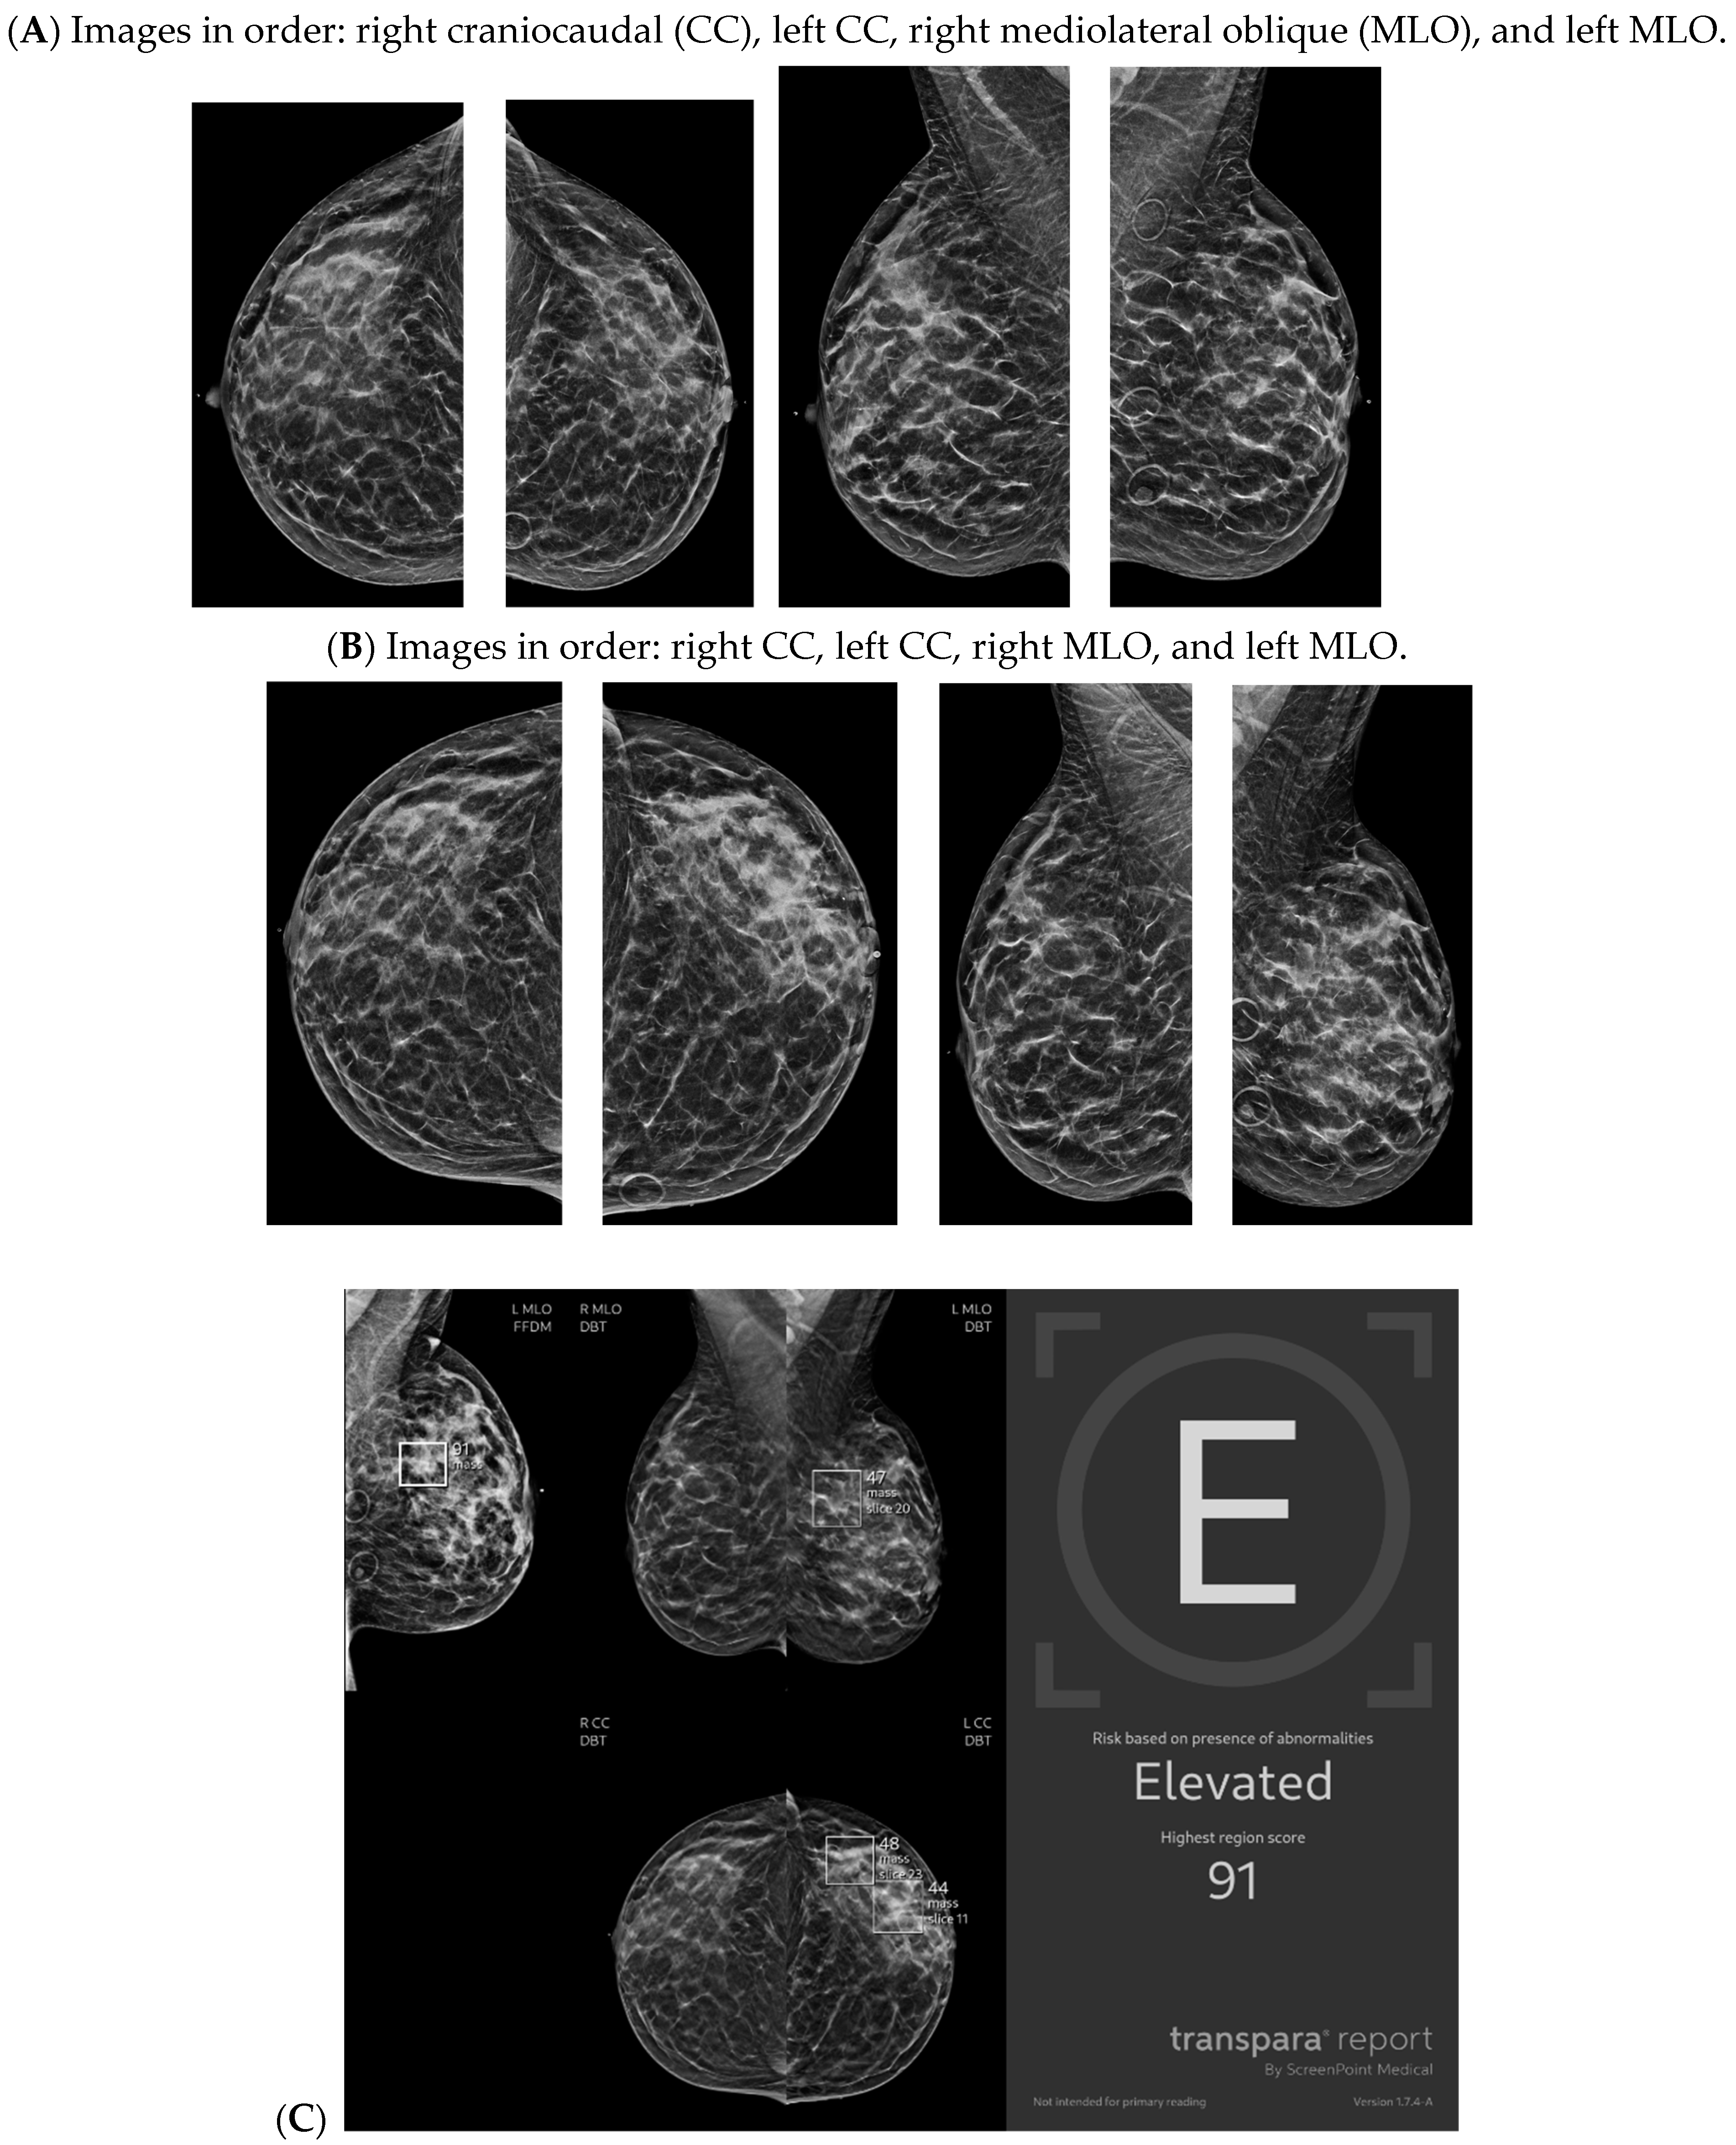

With the widespread implementation of DBT, which increases mammographic cancer detection sensitivity, there are larger volumes of images. This may ultimately increase the risk of reduced accuracy, perhaps due to reader fatigue and increased reading time [24]. There are numerous tomosynthesis AI products available, and at our institution we have implemented the use of Transpara, which is a deep learning-based AI system that uses deep CNN to help improve early-stage cancer detection and sensitivity (at similar specificity), while reducing reading time [24,25]. We view tomosynthesis AI as a valued asset to our clinical practice, as the software highlights potential areas of concern that require additional attention (Figure 1 and Figure 2). However, some areas flagged as concerning are often classically considered benign, such as stable post-lumpectomy sites, stable asymmetries and calcifications, or previously biopsied benign findings. That being said, tomosynthesis AI has been found to have a synergistic effect on cancer detection rate (CDR) when utilized by the radiologist. A study found that radiologist-only CDR was 67.3% and AI-only CDR was 72.7%, but when the radiologist and AI software were used together, the CDR increased to 83.6% [17,25,26]. Lunit INSIGHT MMG, Seoul, South Korea was the diagnostic support software used in this particular study [26].

Figure 2.

New architectural distortion detected by artificial intelligence (AI): A patient in her 50s’ screening mammogram revealed a new area of architectural distortion (circle) in the inner central region of the left breast (A). The AI program Transpara highlighted potential regions of interest, including this suspicious area of architectural distortion on the left breast on the corresponding left CC view; however, AI also highlighted benign areas that were arbitrated out by the radiologist (B). There was no sonographic correlate, so a stereotactic biopsy of this area of architectural distortion was then biopsied under guidance. Pathology yielded invasive lobular carcinoma. Images obtained from the Icahn School of Medicine at Mount Sinai.